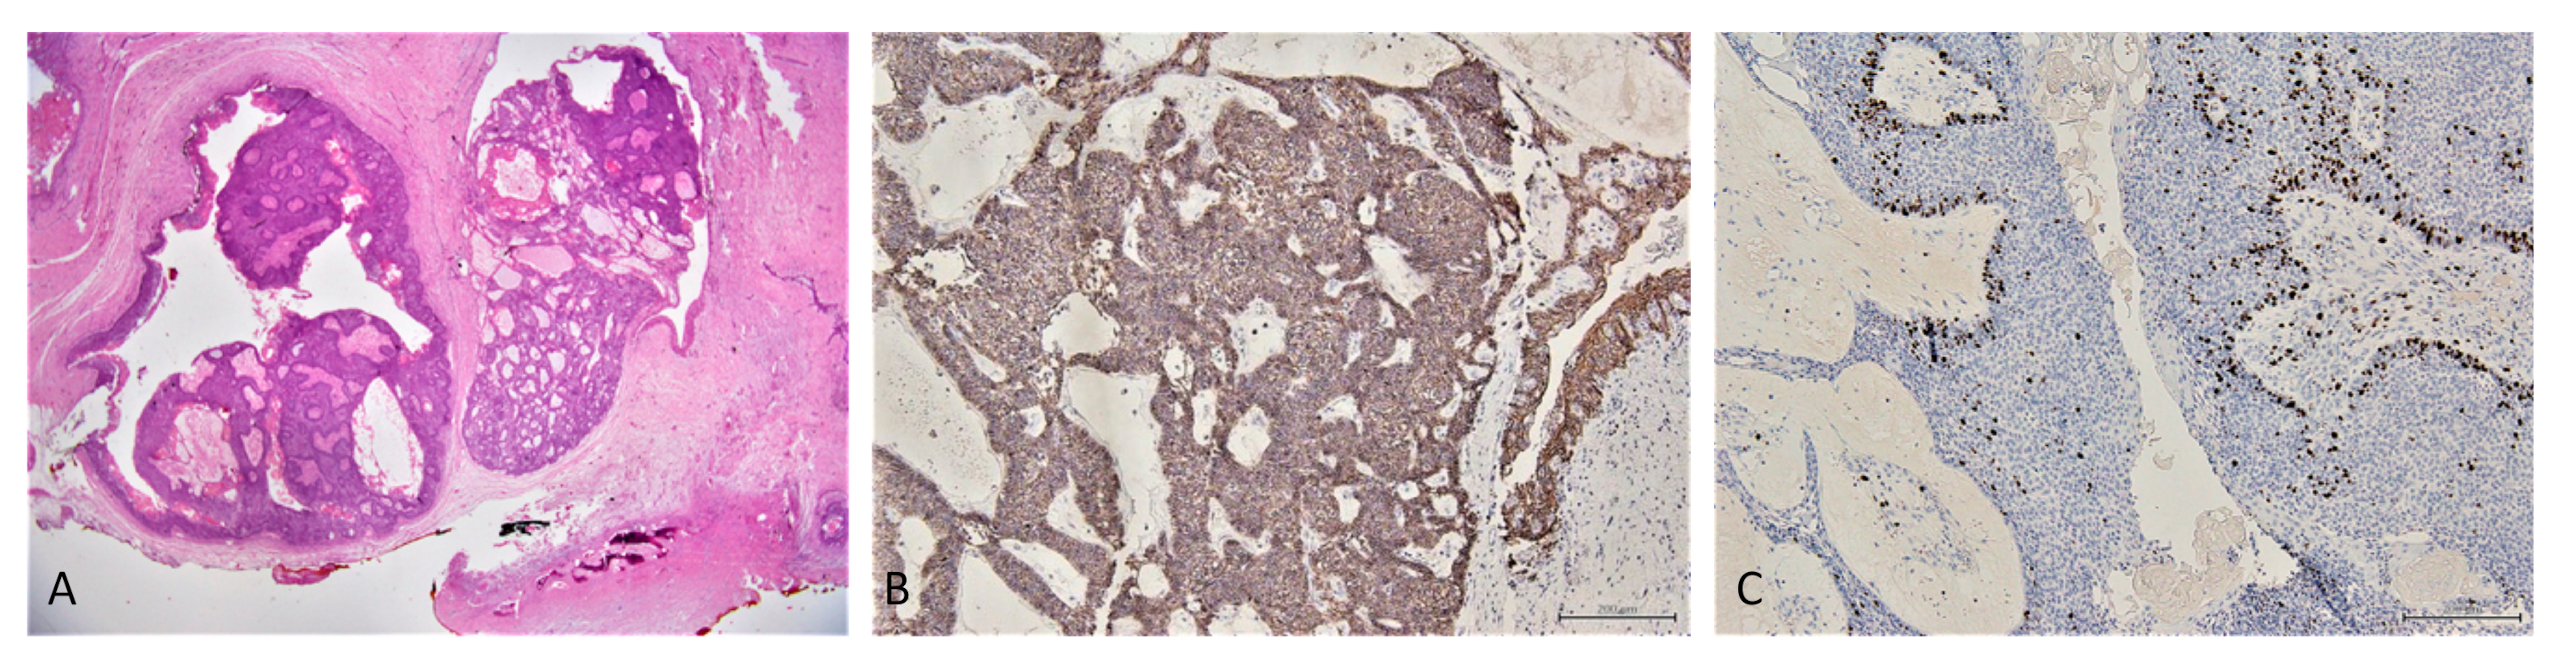

2.2. Incisional Biopsy Findings

2.4. Conventional Ameloblastoma Diagnosis

- Hunter, K.D.; Speight, P.M. The diagnostic usefulness of immunohistochemistry for odontogenic lesions. Head Neck Pathol. 2014, 8, 392–399. [Google Scholar] [CrossRef] [Green Version]

- Sherlin, H.J.; Natesan, A.; Ram, P.; Ramani, P.; Thiruvenkadam, C. Immunohistochemical profiling of Ameloblastomas using cytokeratin, vimentin, smooth muscle actin, CD34 and S100. Ann. Maxillofac. Surg. 2013, 3, 51–57. [Google Scholar] [CrossRef] [Green Version]